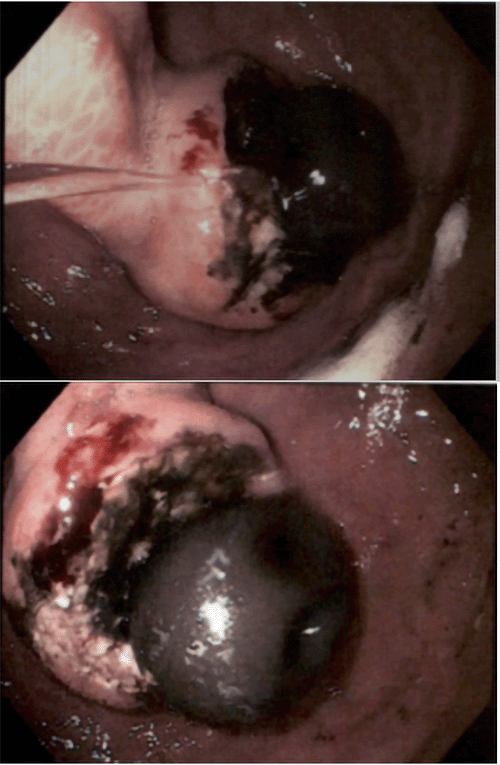

The patient underwent definitive surgical treatment via en bloc resection of the mass. One-centimeter margins were taken grossly in all directions of the tumor edge. The intraabdominal portion of the mass required an anterior gastrectomy, which was kept continuous with the cutaneous mass and separated from normal-appearing stomach using electrocautery. The cephalad margin of the tumor was abutting the lateral segment of the left lobe of the liver, which was divided using electrocautery. Lastly, an additional margin was densely adherent to the transverse colon and required division with a linear stapling device oriented longitudinally not to violate the colonic lumen. The resected specimen contained the old gastrostomy tube, the entire tumor, and involved portions of the stomach, liver, and colon (Figure 2). The resulting gastrostomy was repaired, and a new gastrostomy tube was placed and sited at healthy tissue at the right anterior abdominal wall. Reconstruction of the abdominal wall defect was achieved with a local advancement flap in conjunction with the placement of 15 × 15 cm Strattice mesh, and a wound vac was placed.

Figure 2. Intraoperative Images. Published with Permission

A) Cutaneous squamous cell carcinoma surrounding gastrostomy tube

B) specimen of en-bloc resection

C) resultant abdominal wall defect with newly-sited gastrostomy tube